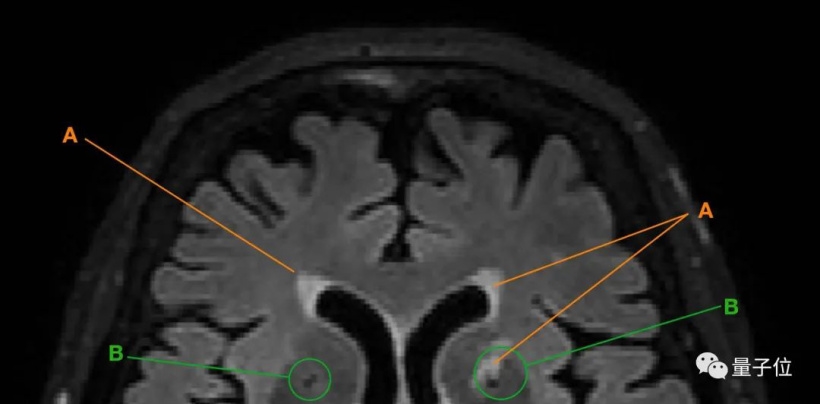

得出以上结论,研究人员主要是通过追踪老人大脑中脑白质高信号(WMH)和腔隙的变化来实现的。

▲ A 为脑白质高信号;B 为腔隙

以上两种现象都是脑小血管病(CSVD)的主要表现。

也就是说,当老人的大脑中出现脑白质高信号、腔隙变多变大等情况,就意味着老人的大脑可能在发生退化。